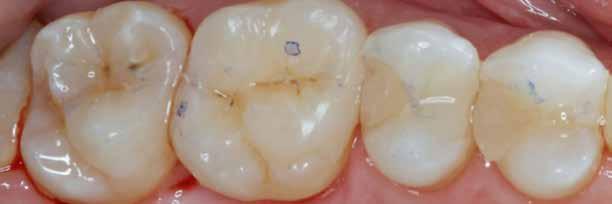

A felesleges kompozit eltávolítását és a derékszögű záródási vonal kialakítását a 6–9. képek szemléltetik.

8. ábra: A durva finírozás után kialakult szélek.

9. ábra: Hat hónapos kontroll.

10. ábra: Polírozópaszta felvitele.

11. ábra: A végső polírozás.

12. ábra: A premoláris fogak preoperatív állapota.

13. ábra: A premoláris fogak postoperatív fotója.

14. ábra: Egy moláris fog preoperatív állapota.

15. ábra: Egy moláris fog postoperatív fotója.